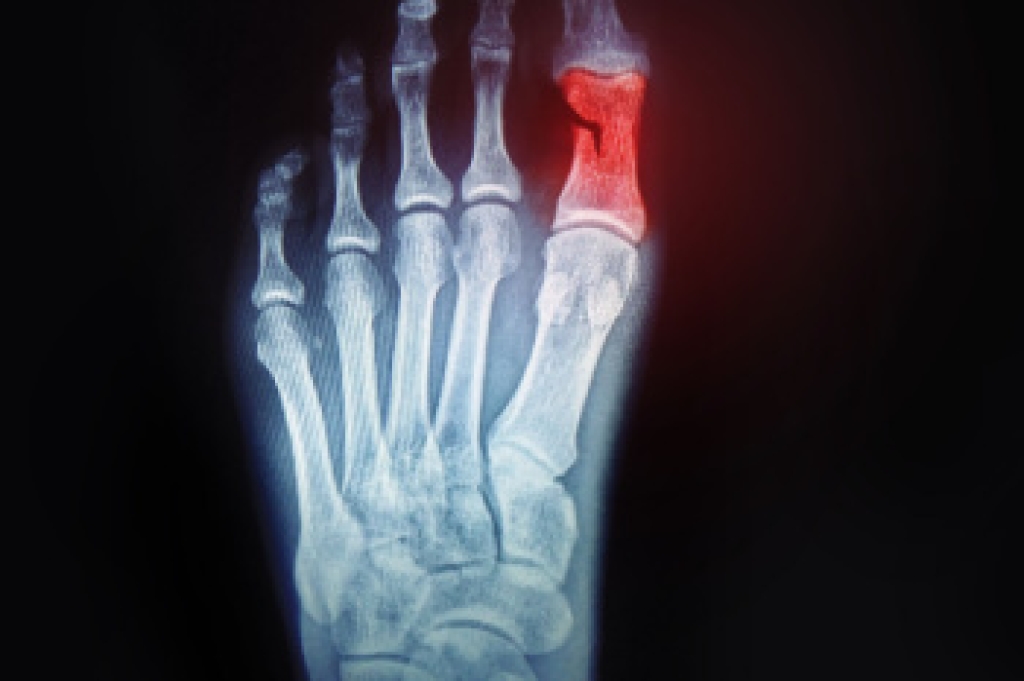

Due to the wide variety of potential causes of ankle pain, podiatrists will utilize a number of different methods to properly diagnose ankle pain. This can include asking for personal and family medical histories and of any recent injuries. Further diagnosis may include sensation tests, a physical examination, and potentially x-rays or other imaging tests.